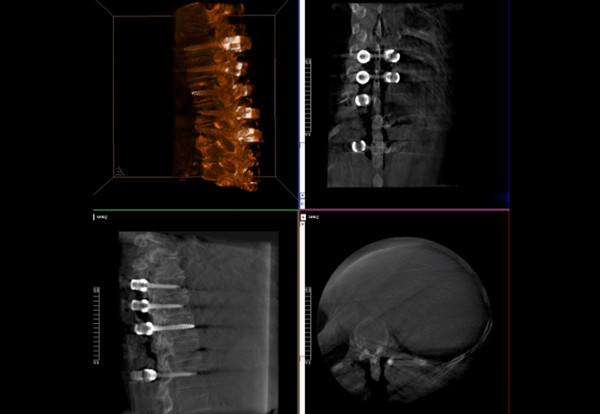

普爱医疗术中三维导航C臂快速生成横断面、矢状面、冠状面断层图像和三维立体图像,方便医生确认手术部位。C形臂的大平板带来出色的显示视野,可以更好的显示手术部位全局情况,确保手术规划及执行的准确性。

三维影像检验螺钉植入效果

一台C形臂

二维三维影像 皆能完好呈现